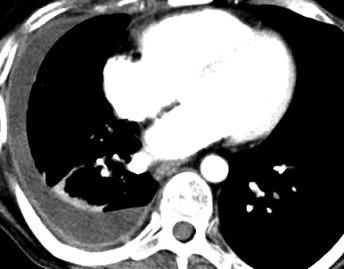

Signos radiológicos TC

Hallifax RJ et al. State-of-the-art: Radiological investigation of pleural disease Respiratory Medicine 2017

Nivel hidroaéreo o burbujas

Forma lenticular o elíptica Ángulos obtusos

> Grasa Extrapleural (60-80%)

Situación no gravitacional (no siempre)

Compresión de estructuras pulmonares

Límite muy bien definido Tabicación

Empiema

El derrame paraneumónico se convierte en complicado en 5-10% de los casos